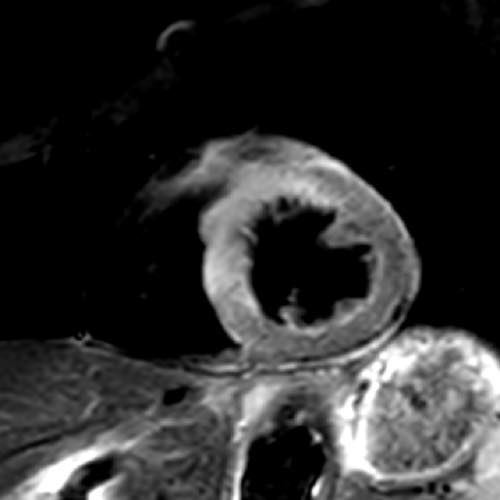

【非造影心臓MRI】

腎臓の機能が低い場合には、造影剤を用いる冠動脈CT検査は出来ません。MRIでは、造影剤を使用しなくても冠動脈や心臓の機能、心筋の性状を評価する事ができます。

非造影のMRI冠動脈画像(左,中央)にて,右冠動脈に狭窄病変が疑われ,カテーテルによる冠動脈造影検査(右)でも,同じ部位に狭窄病変が認められました.

急性心筋梗塞の1例:シネMRI画像(左から中央)では、左心室の一部で収縮が低下している領域があり、心筋の浮腫(T2)画像では、同部位に信号値の高い部分を認め、急性心筋梗塞の所見となります。